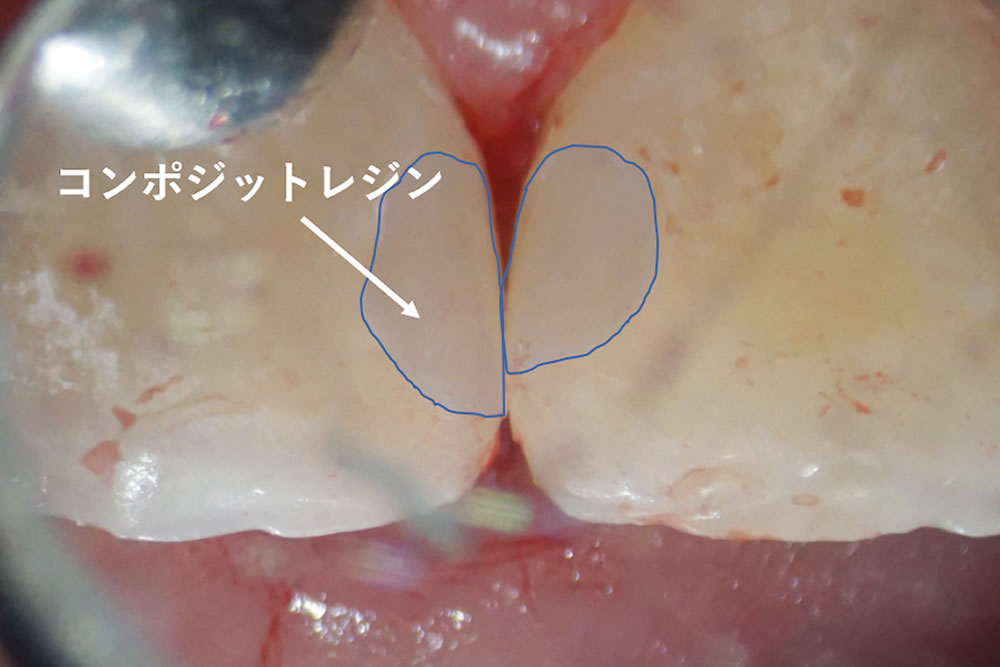

行徳スマイル歯科で実施したCR治療の症例をご紹介

正面(写真左)から見ると、何も異常がないように見えますが、上顎前歯の裏側(隣り合った歯と歯の接触している部分)が虫歯になっていました。

レントゲンで虫歯部分を確認

レントゲンで確認すると、以前の治療で修復した部分に隙間が生じていました。詰め物と虫歯感染歯質を丁寧に取り除いていきます。

虫歯除去後にCRを充填して治療完了

象牙質まで達していた虫歯(C2/中度虫歯)を、丁寧に取り除いた後にCRを充填して治療完了です。CR(コンポジットレジン)による虫歯治療は、一度の治療で完治していますが、なるべく長持ちさせるために患者様ご自身で、術後の管理(今回の場合は歯ブラシ+フロスの使用など)と定期的な歯科医院でのチェックが必須になります。